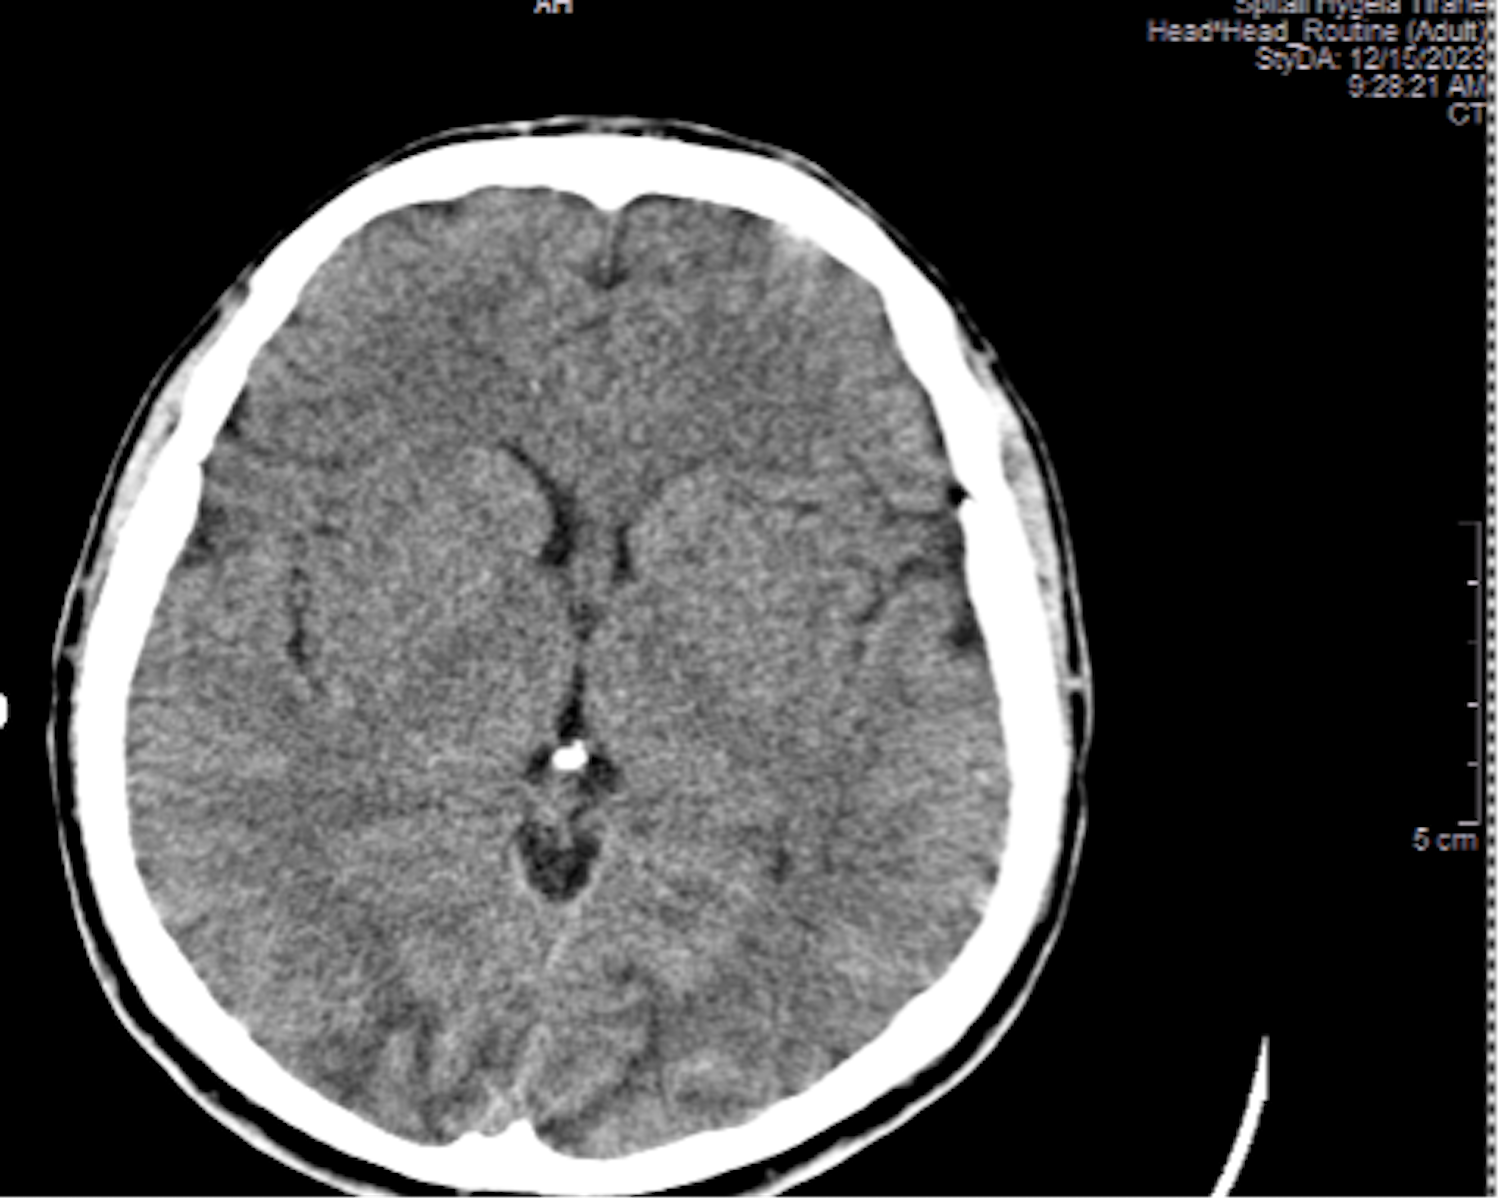

Results: A 23-year-old male patient who had been receiving dialysis for four years underwent a kidney transplant with a living donor - his mother. The primary disease leading to end-stage renal disease (ESRD) was rapidly progressing glomerulonephritis. At the time of diagnosis, he also had high blood pressure readings which remained uncontrolled during the dialysis period, complicated by left ventricular hypertrophy and hypertensive retinopathy, however, the head MRI was normal. During the last year of dialysis, the blood pressure was normalized under multidrug antihypertensive therapy, which included doxazosin, amlodipine, hydralazine, metoprolol, minoxidil, and irbesartan. Post-transplant surgery, diuresis was immediately established. Induction therapy was conducted with ATG, and maintenance therapy included tacrolimus, MMF, and prednisone. The values of creatinine and urea were decreasing. On the fifth postoperative day, the patient experienced seizures, altered mental status, headaches, and visual disturbances but no neurological deficits. His vital signs stabilized after 2-3 minutes post-seizure with the following parameters: blood pressure 150/90 mmHg, heart rate 110/minute, respiratory rate 17/minute, oxygen saturation 97%, body temperature 36.6°C, lactate level 6 mmol/L, pH 7.35, and bicarbonate (HCO3) 22 mmol/L. The neurologist recommended an urgent head CT scan, which showed Posterior Reversible Encephalopathy Syndrome (PRES). The level tacrolimus of tacrolimus was 8.6 ng/dl.